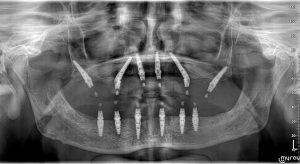

Ο D-r Rafid Hussain, επικεφαλής χειρουργός οδοντικών εμφυτευμάτων στο Κέντρο Εμφυτευμάτων της Σόφιας, πραγματοποίησε πρόσφατα την πρώτη χειρουργική επέμβαση με πτερυγοειδή εμφυτεύματα στη Βουλγαρία. Αυτό κατέστη δυνατό χάρη στη χρήση χειρουργικών οδηγών και καινοτόμων ψηφιακών πρωτοκόλλων, τα οποία επέτρεψαν την τοποθέτηση οδοντικών εμφυτευμάτων στο πτερυγοειδές οστό με εξειρετική ακρίβεια, παρέχοντας ασφαλή βάση για μια αποκατάσταση πλήρους τόξου με βάση 6 εμφυτεύματα (ALL-ON-6).

Η χρήση χειρουργικών οδηγών εξασφάλισε την επιτυχία της επέμβασης, με τον ασθενή να είναι πλέον σε θέση να απολαμβάνει ένα πλήρες σετ ακίνητων δοντιών, προσφέροντάς του αυξημένη λειτουργικότητα, άνεση και αυτοπεποίθηση.